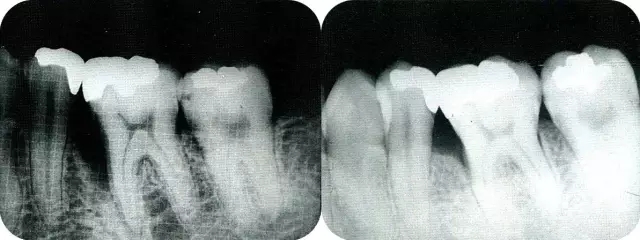

▲圖7-1  左下6近中可觀察到3壁性垂直性骨缺損。此病例考慮到齦瓣供血關(guān)系,在前磨牙部位進行了減張切開,沒有進行縱切開。并利用刮治器、牙周外科用車針進行了徹底的骨缺損部位搔刮。

▲圖7-2  術(shù)前x片。確認存在垂直性深骨缺損。

▲圖7-7  術(shù)前,術(shù)后的x片。確認出現(xiàn)骨再生,牙槽嵴硬線。